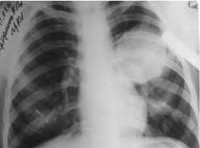

Эхинококкоз легких

Эхинококкоз легких протекает с повышением температуры тела, интоксикационным синдромом, болью в груди, кашлем, кровохарканьем. Давление кисты на легочную ткань приводит к формированию ателектазов легких. При прорыве пузыря в бронхи развивается сильный кашель, цианоз, нередко — аспирационная пневмония. Крайне опасным осложнением легочного эхинококкоза является прорыв кисты в плевру и перикард, что может привести к анафилактическому шоку, резкому смещению средостения, тампонаде сердца и внезапной смерти. Инфицирование эхинококковой кисты сопровождается формированием абсцесса легкого.

Человек заражается эхинококкозом преимущественно перорально, и в связи с гематогенным путем распространения онкосферы могут поражать любой орган, любую ткань, но чаще всего печень (44 — 85%), затем легкие (15 — 20%) в более редких случаях по большому кругу кровообращения — почки, кости, головной и спинной мозг и другие органы.